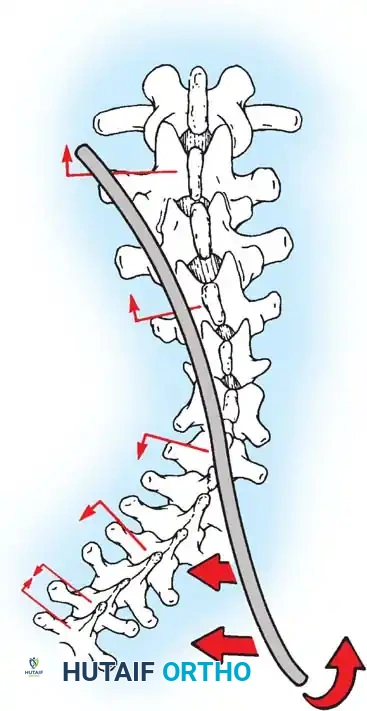

Biomechanics of Bone Grafting

Bone graft incorporates most effectively under compressive loads and is biologically disadvantaged in environments of distraction. Therefore, in scoliosis correction, if autogenous bone is limited, it should be preferentially concentrated on the concave side of the curve, which is subjected to compressive forces, rather than the convex side, which experiences tension. Furthermore, the farther the fusion mass is placed from the instantaneous axis of rotation, the more effectively it will neutralize movement across that axis.

The Moe Technique (Lumbar Spine)

In the lumbar spine, the facet joints are oriented in a more sagittal plane, necessitating a modified approach.

Fig. 38-27: The Moe technique adapted for lumbar facet fusion, addressing the sagittal orientation of the joints.

- Utilize a small osteotome or a needle-nose rongeur to resect the adjoining joint surfaces.

- This creates a distinct rectangular defect within the sagittally oriented joint space.

- Pack this defect forcefully with cancellous bone graft.

- Proceed to decorticate the entire exposed posterior elements (laminae and transverse processes) using Cobb gouges, always directing force away from the spinal canal.